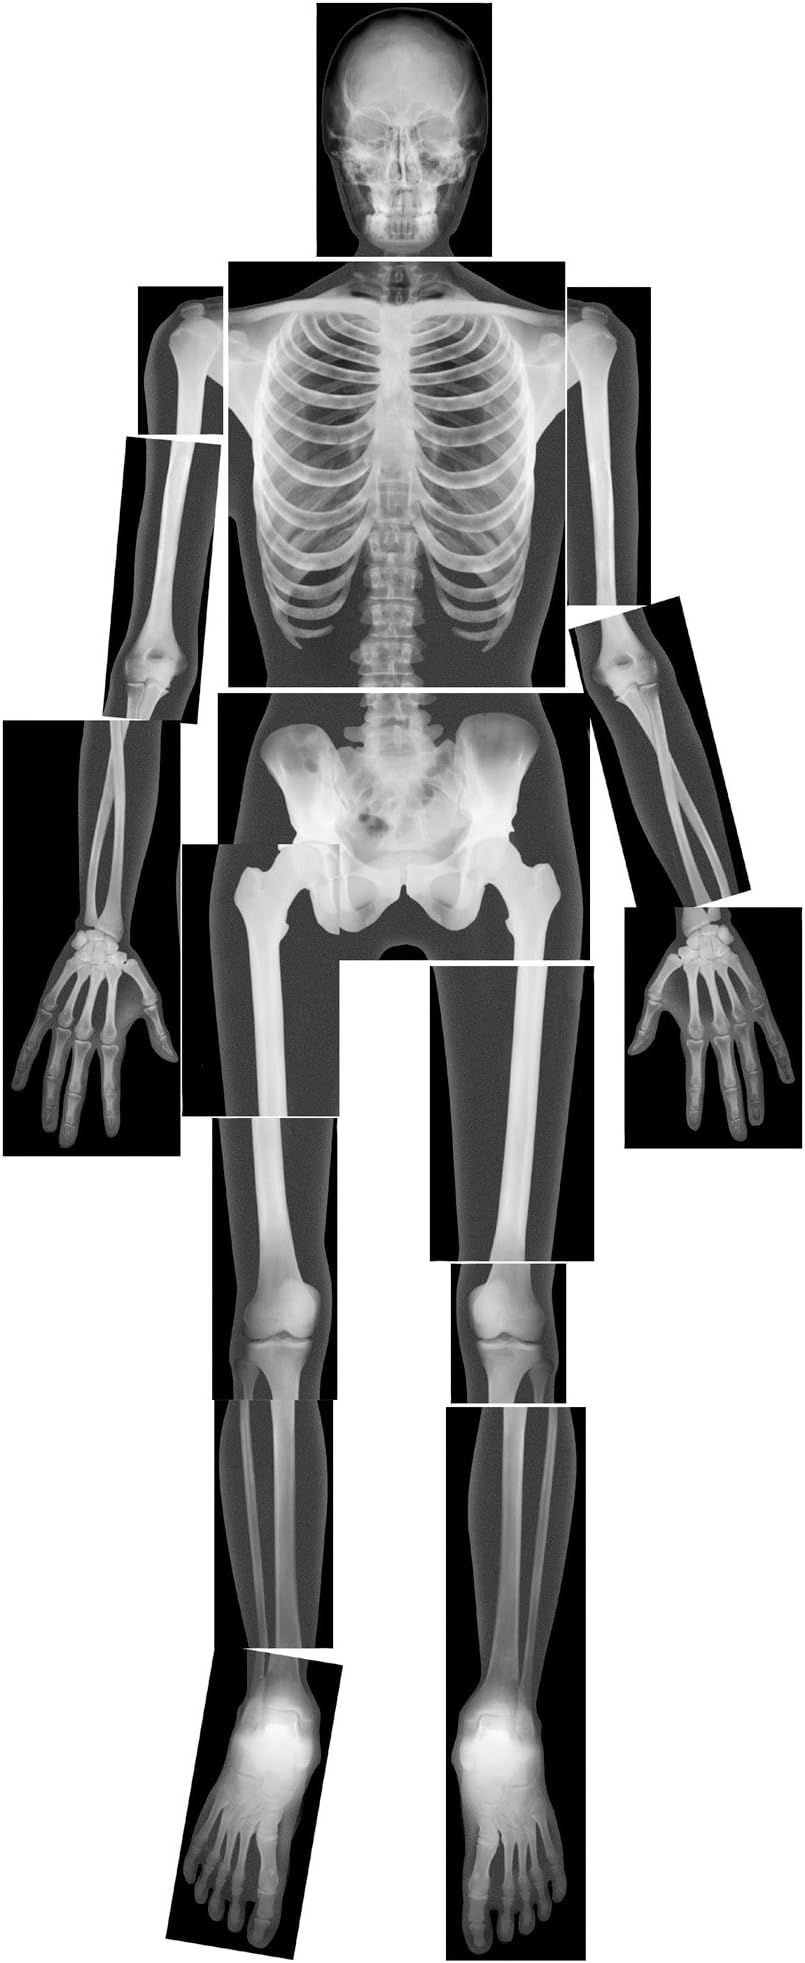

True To Life Human X-Rays

RoylcoTrue To Life Human X-Rays

| Set Name | Human Skeleton X-Ray Set |